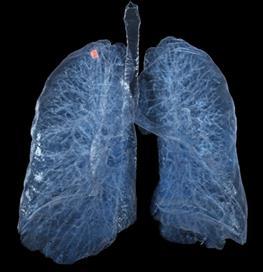

Lung cancer screening Chest CT Pulmonary lesions – Chest X-Ray